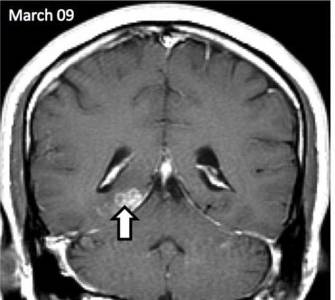

Ez az első alkalom a férfi megfordult, hogy az orvosok négy évvel ezelőtt, ő fejfájásra panaszkodott, és furcsa szagot. Az orvosok, akik végzett felmérés, megzavarodtak kóros területeket az agyban, hogy az MRI kimutatta. Megfigyelések a következő években azt mutatta, hogy a rendellenesség által mozgatott öt centiméter, írja a The Guardian.

Az orvosok a St. Thomas Kórház beteg HIV-tesztet, a szifilisz és a különböző fertőző betegségek. Ennek eredményeként, a biopszia jelenlétét mutatta galandféreg. Genetikai Wellcome Trust Sanger Institute Cambridge megállapítottuk, hogy ez egy rendkívül ritka parazita ismert Spirometra erinaceieuropaei.